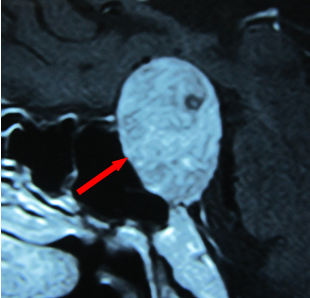

紅箭頭示垂體瘤

腦內(nèi)垂體是人體內(nèi)分泌激素最多的器官之一,其功能重要并復(fù)雜。近年來垂體瘤的發(fā)生率有上升趨勢,并是第三位的腦內(nèi)腫瘤(約占10%左右),但它屬于良性腫瘤。其臨床表現(xiàn)多種多樣,主要取決于病理類型(8種類型)。其中的泌乳素細(xì)胞腺瘤(垂體腺瘤)最常見于青春期女性,臨床表現(xiàn)有閉經(jīng)、泌乳及不育等癥狀群,也是很多月經(jīng)異常女性到處就醫(yī)最后確診的疾病之一。其他類型的垂體瘤也可能導(dǎo)致月經(jīng)異常及不育。診斷垂體瘤必須具體以下三方面:臨床癥狀、激素水平的異常及垂體影像學(xué)上的異常。治療上有手術(shù)、藥物及放射性治療的三種方案。大多數(shù)垂體瘤的預(yù)后良好,特別是對生理性月經(jīng)的恢復(fù)明顯有效。